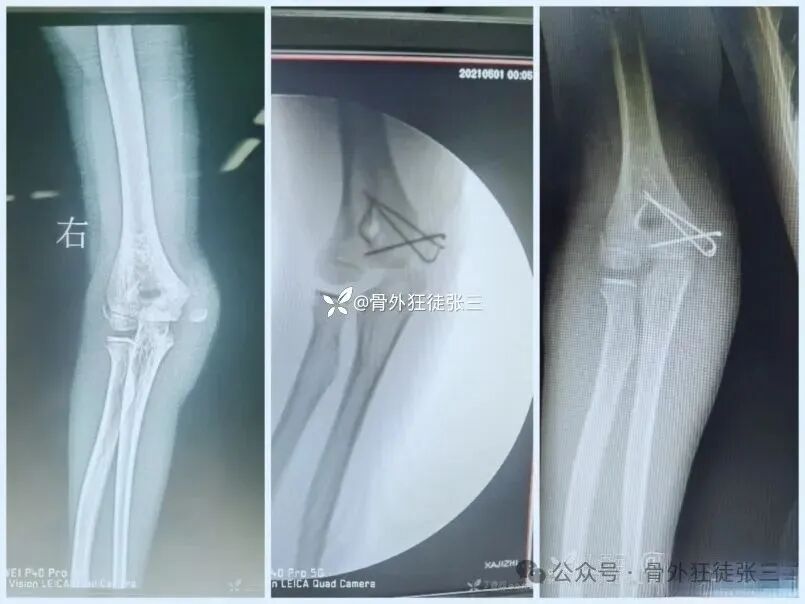

病例1:髁上骨折

桡侧三枚针发散固定

石膏固定2周,肘关节支具2周

4周复查,带针肘关节活动度正常

6周拔针